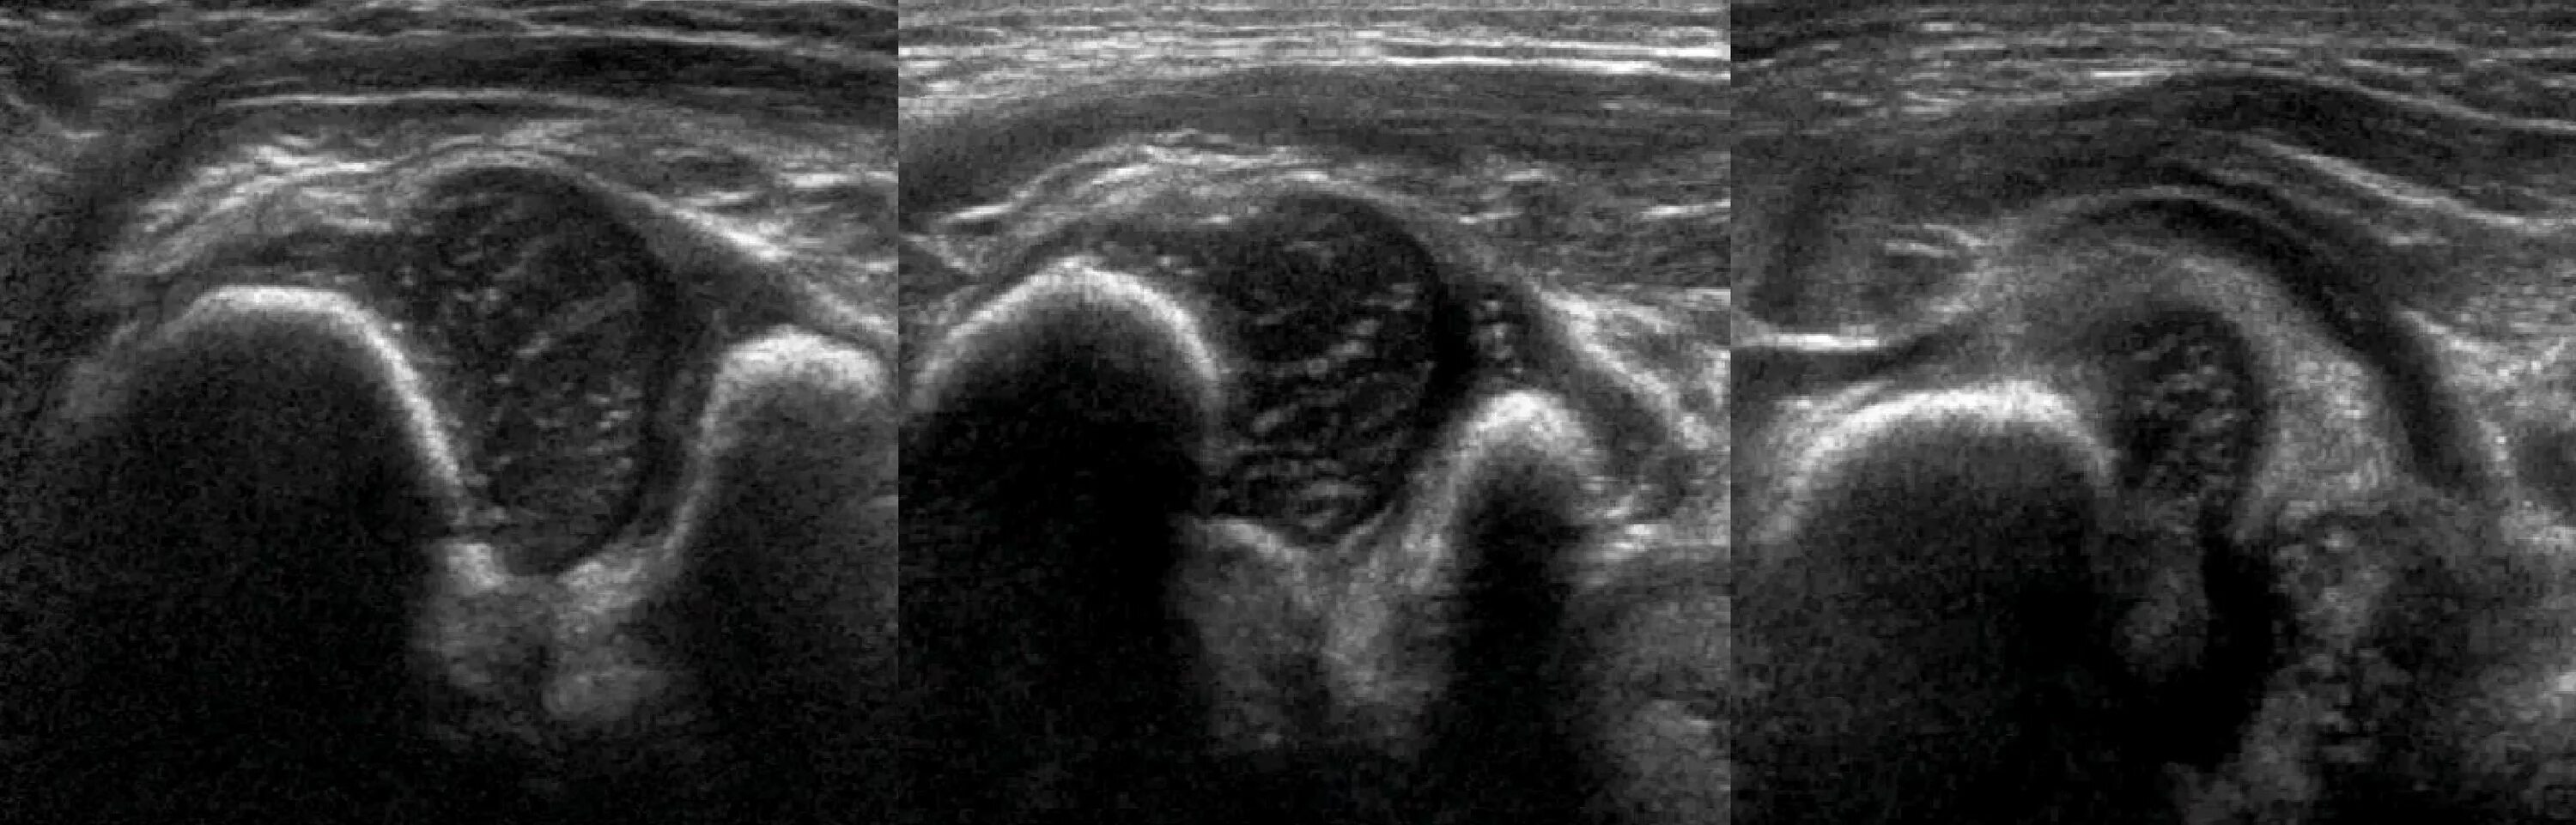

Делают ли узи тазобедренного сустава